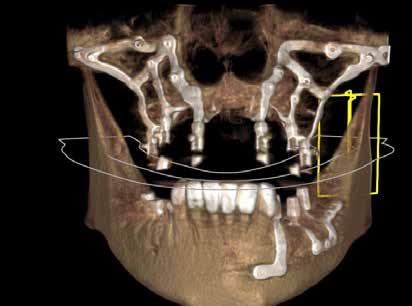

Eaglegrid: singolo intervento a carico immediato in gravi atrofie ossee

Risolvere le atrofie ossee, può essere un compito complica to per i clinici. Le richieste dei pazienti sono ormai mirate a risolvere le edentulie parziali o totali con tempi sempre più corti e con il restauro protesico in tempi corti o ancora meglio caricamento immediato degli impianti. L’implantologia, cosi definita tradizionale, ovvero con impianti endossei riesce a rispondere a queste esigenze in modo concreto nella maggior parte dei casi.

Ci sono però situazioni cliniche, in cui il riassorbimento dell’os so alveolare è troppo avanzato lasciando spazio solo ed esclu sivamente all’osso basale. Sono state proposte tecniche rige nerative, utilizzando materiali di ogni tipo. I risultati non sono tutti favorevoli a questo tipo di approccio e con una soddisfa zione dei pazienti non ottimale considerando che è necessario affrontare più interventi con tempi di guarigione lunghi e senza poter posizionare imme diatamente la protesi. Il proto collo Eaglegrid, invece riesce a

rispondere concretamente alle esigenze dei clinici e dei pa zienti. Consiste nell’espressio ne massima dell’implantologia digitale, portando una rivolu zione del campo dell’implanto logia subperiostale. Gli impianti subperiostali erano stati abban donati per le difficolta tecniche, dovute a tecnologie troppo ru dimentali. EAGLEGRID invece segue i casi a 360 gradi, inizian do la progettazione dei casi a partire dai restauri protesici con cui i clinici vogliono riabilitare i pazienti.

Viene quindi eseguita una pro tesi guida, utilizzata come dima radiologica, con cui verrà ese guito l’esame radiologico ovve ro una CBCT. La dima radiolo gica consente al team di clinici, bio ingegneri ed informatici di sviluppare la struttura dell’im pianto subperiostale da stam pare con tecnica laser melting con le corrette emergenze pro tesiche, rispettando ciò che ve ramente il clinico vuole ottene re. La precisione del manufatto, prodotto in laser melting, è quindi al centesimo di millime

tro e presenta a livello micro scopico una struttura perfetta, priva di difetti. Grazie alle tec nologie digitali, le possibilità di riabilitazione sono infinite e si può quindi riabilitare l’elemen to singolo come nel caso delle agenesie, edentulie parziali, sia nel mascellare superiore che in feriore o arcate totali. È anche possibile utilizzare in sinergia gli impianti endossei o pterigoidei nel caso fosse ne cessario.

EAGLEGRID, è stata la prima soluzione digitale italiana per la chirurgia sottoperiostale, può quindi vantare ormai un enorme numero di casi con fol low-up di 10 anni. Molti clinici da anni si affidano a Eaglegrid, per risolvere i casi di gravi atro fie con un approccio definito stress-free, considerando che viene fornito un servizio com pleto, dalla progettazione all’at to chirurgico direttamente dal team di EAGLEGRID.

Per concludere è un trattamen to che si inserisce nell’implan tologia di tipo NON endossea, che sfrutta l’intimo appoggio ad una struttura ossea nella sede sottoperiostale, piuttosto che la sua integrazione all’in terno di essa. È una metodica riservata alla risoluzione di gra

vi atrofie verticali e trasversali, dove non è possibile eseguire una implantologia endossea e dove la rigenerativa è scon sigliata. EAGLEGRID rappre senta un prodotto innovativo frutto della coniugazione della radiologia digitale accoppia ta alla produzione CAD CAM. Consente al clinico di ipotizzare la risoluzione di qualsiasi caso di atrofia anche marcata in un solo intervento, garantendo an che il carico immediato. Il pro tocollo, brevettato, è certificato secondo le più recenti direttive in materia implantare.

L’estrema flessibilità della me todica si può applicare da un singolo dente a selle come ad intere arcate sia mascellari che mandibolari. Sempre più clinici e pazienti richiedono un tratta mento con EAGLEGRID. L’alta predicibilità di risultato è uno dei motivi di successo di EAGLEGRID anche a livello inter nazionale a riprova che il den tale MADE IN ITALY, ancora una volta può essere di esempio in altri paesi.

Abbiamo rivisitato in chiave di gitale una metodica che grazie a noi sta rivivendo una nuova giovinezza ampliando di molto gli orizzonti dei trattamenti im plantari.